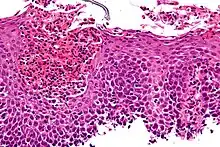

| Micrograph showing eosinophilic esophagitis. H&E stain. | |

Endoscopically, ridges, furrows, or rings may be seen in the esophageal wall. Sometimes, multiple rings may occur in the esophagus, leading to the term "corrugated esophagus" or "feline esophagus" due to the similarity of the rings to the cat esophagus. The presence of white exudates in the esophagus also suggests the diagnosis.[13] On biopsy taken at the time of endoscopy, numerous eosinophils can be seen in the superficial epithelium. A minimum of 15 eosinophils per high-power field are required to make the diagnosis. Eosinophilic inflammation is not limited to the esophagus alone and does extend through the whole gastrointestinal tract. Profoundly degranulated eosinophils may also be present, as may micro-abscesses and an expansion of the basal layer.[3][10]

Endoscopic mucosal biopsy remains the gold standard diagnostic test for EoE and is required to confirm the diagnosis.[8] Endoscopy with biopsies of the esophagus has a 100% sensitivity and 96% specificity for diagnosing eosinophilic esophagitis.[8] Biopsy specimens from both the proximal/mid and distal esophagus should be obtained regardless of the gross appearance of the mucosa. Specimens should also be obtained from areas revealing endoscopic abnormalities.[2] 2-4 biopsies should be obtained from both the proximal and distal esophagus to obtain adequate tissue samples for the detection of EoE.[2] A definitive diagnosis of EoE is based on the presence of at least 15 eosinophils/HPF in the esophageal biopsies of patients with exclusion of other causes of eosinophilia in the esophagus including gastroesophageal reflux disease (GERD), achalasia hypereosinophilic syndrome, Crohn's disease, infections, pill esophagitis, or graft vs host disease.[8] Endoscopy is usually indicated after treatment is started for EoE to confirm histologic remission.[8]